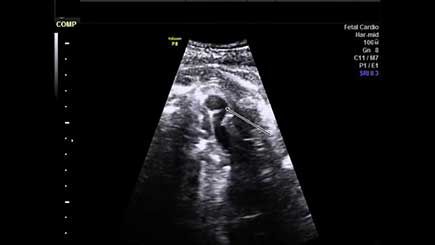

Challenge your diagnostic skills: Can you identify this anomaly?